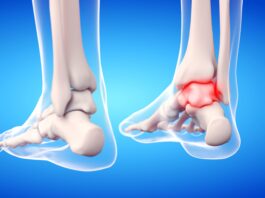

Frattura di caviglia: benefici della crioterapia di terza generazione preoperatoria

Abbastanza frequente tanto tra gli anziani, quanto tra i giovani, le fratture di caviglia vengono spesso trattate con...